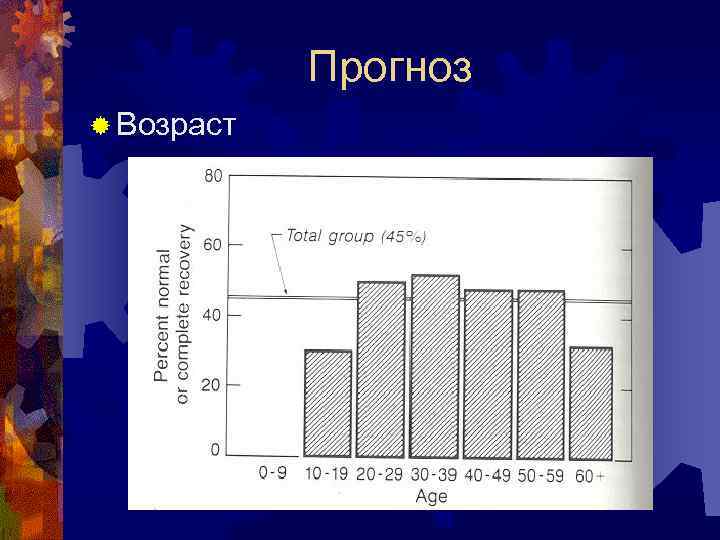

Прогноз ® Возраст